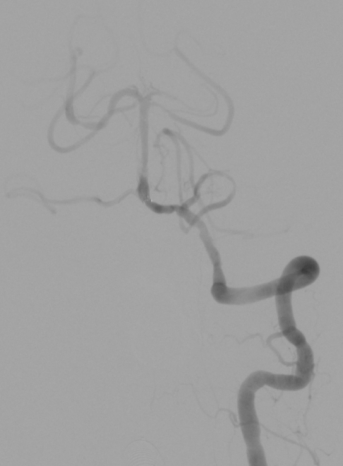

入院颅脑CT未见明显异常;头颈CTA提示基底动脉闭塞;

DSA示:基底动脉下段闭塞。

SacSpeed®2.0mm×15mm球囊

Neuroform EZ支架 4mm✕20mm